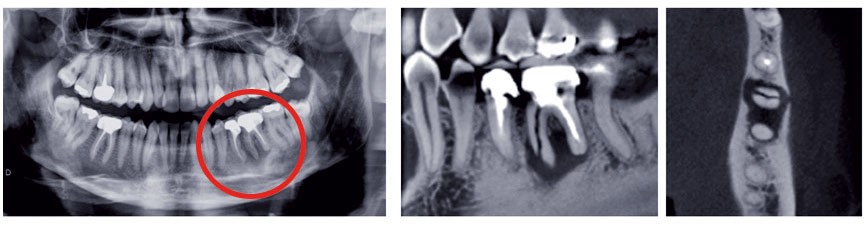

Une structure anatomique n’est radiologiquement visible que si le rayon directeur (axe du faisceau Rx incident) est tangent à cette structure. Une fracture radiculaire longitudinale ne sera mise en évidence qu’aux conditions d’une orientation favorable et de dimensions suffisantes (fig. 2).

L’imagerie moderne (3D)

Initiée par le scanner Rx, complétée par le Cone Beam, elle restitue le volume anatomique dans ses trois dimensions par calcul informatique. Les principes d’acquisition sont…